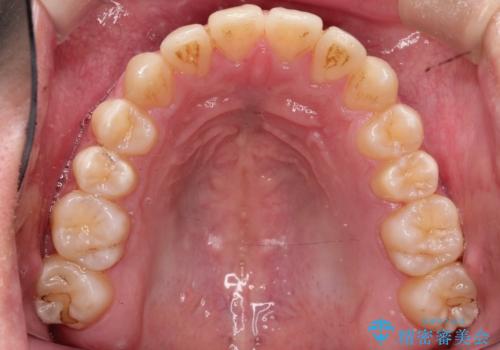

【MSE+インビザライン】前歯のガタガタ

- 前歯の凸凹を主訴に来院されました。

上の歯のアーチが狭窄していたため、骨の幅を広くするためにMSE(急速拡大装置)を使用してからインビザライン にて治療を行いました。

MSE(急速拡大装置)を用いたことで、短期間で奥歯の噛み合わせもしっかりと治すことができました。